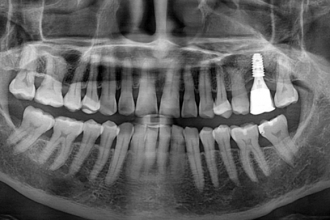

임플란트